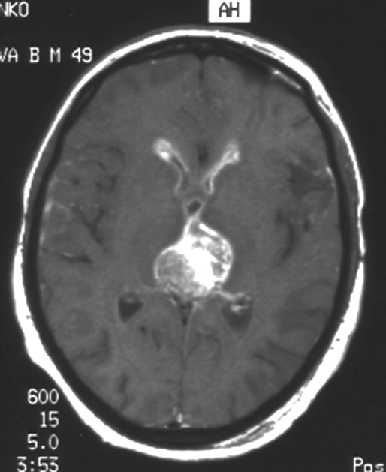

На МРТ обычно имеют вид узла дольчатого строения без четких границ с мелкими кистами в структуре опухоли. Введение гадолиния приводит к гетерогенному усилению МР-сигнала (рис. 2).

Рисунок 2. Хориокарцинома шишковидной железы (МРТ, Т1-взвешенное изображение)